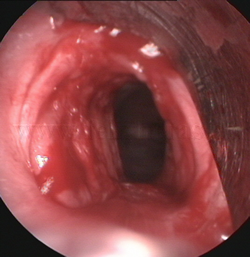

Tumores

traqueales |